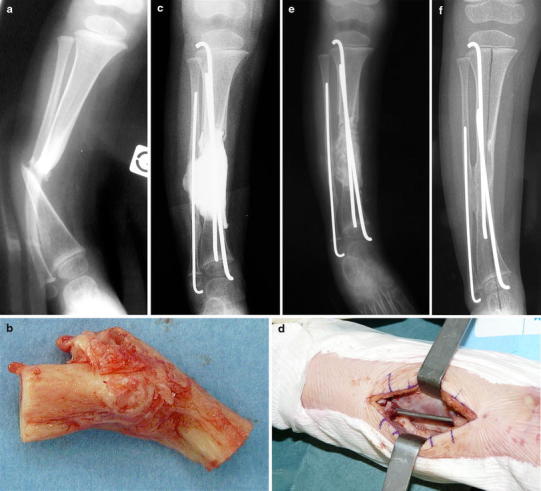

Fig. 5.

Case 5. a Anteroposterior radiograph showing CPT of the distal third of the tibia in a 20-month-old girl. b Operative specimen of the excision of the pseudarthrosis and the abnormal periosteum. c Postoperative radiograph of the first stage of the induced membrane technique. Cement spacer bridging both the tibial and the fibular gap, and intramedullary pinning of the tibia and the fibula. d Intraoperative view of the induced membrane after removal of the cement spacer opened in continuity with the periosteum of the proximal and distal remaining tibia. e Postoperative radiograph of the second stage of the induced membrane technique after grafting in the biological chamber surrounded by the membrane. f Radiograph at the last follow-up (2.4 years)